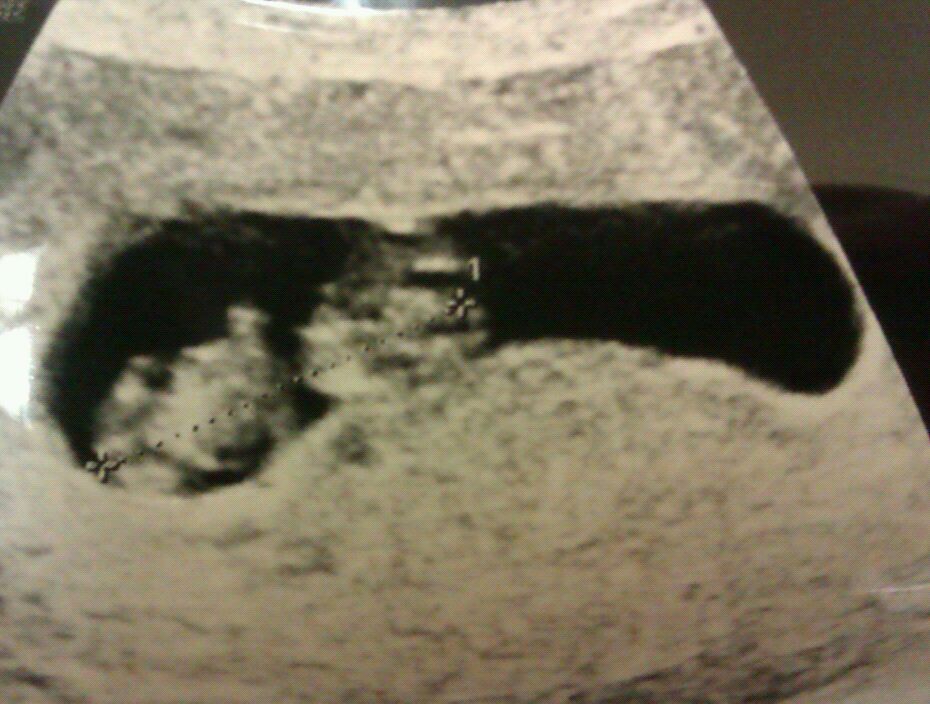

My friend is desperate to find out the sex of her baby! Any guesses greatly appreciated!

No nub in the pic

Skull theory? That's definitely in this pic lol

maybe girl

I don't know much about the skull theory but it looks like my ds3 12 week scan so I would guess boy on the skull